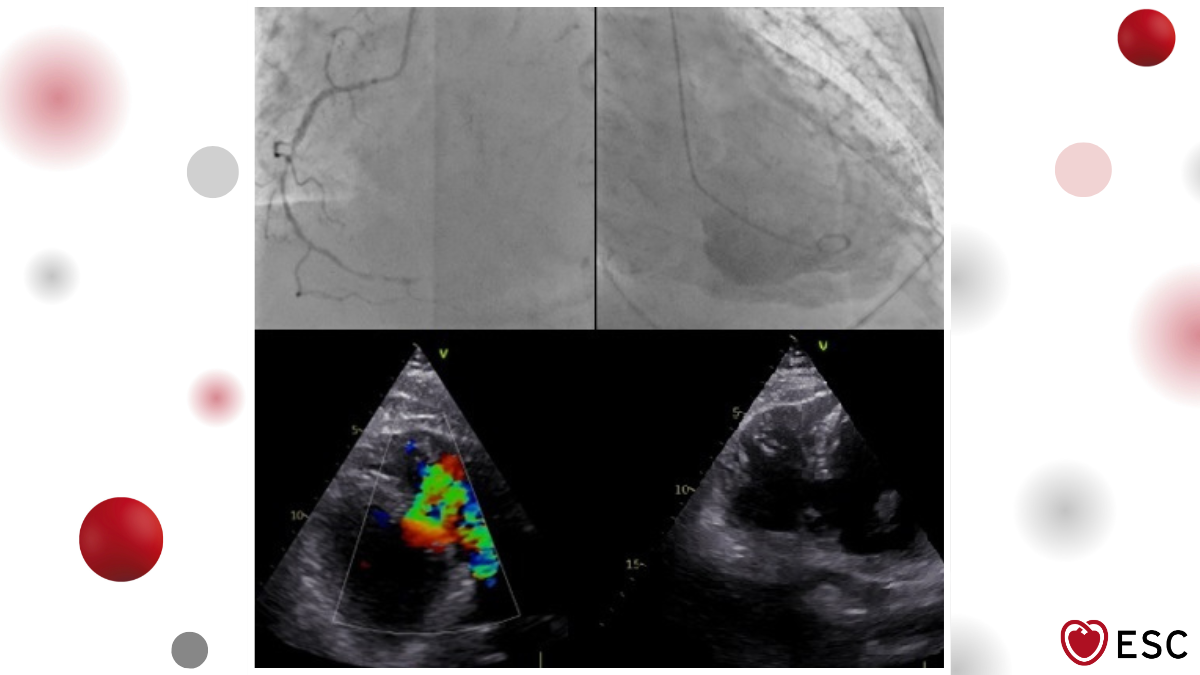

Image of the Week 21 January 2026

Doctor Astrid Declercq